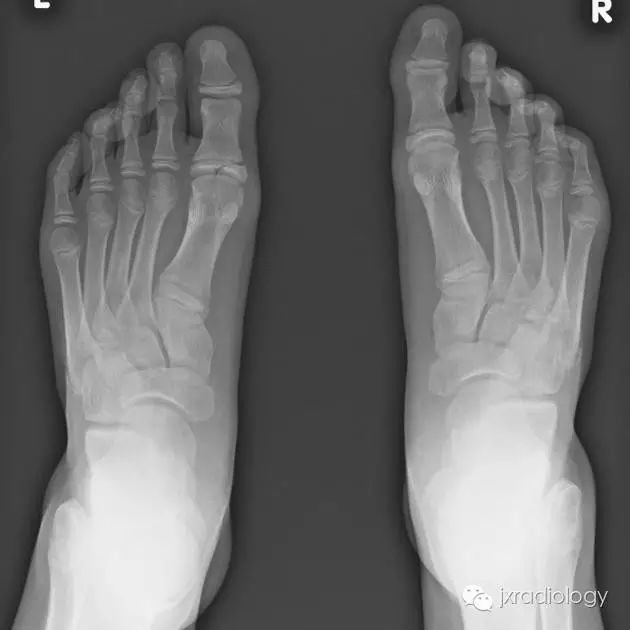

骨骺裂是一种正常变异。它可以是单侧或双侧,最常见的部位是足的第1趾近节趾骨的骨骺。

X线平片显示骨骺见透亮状裂隙影;透亮影的边缘是可变的,可能是锐利的或不规则的。骨骺裂可保留至生长板的融合。

病例图片:骨骺裂